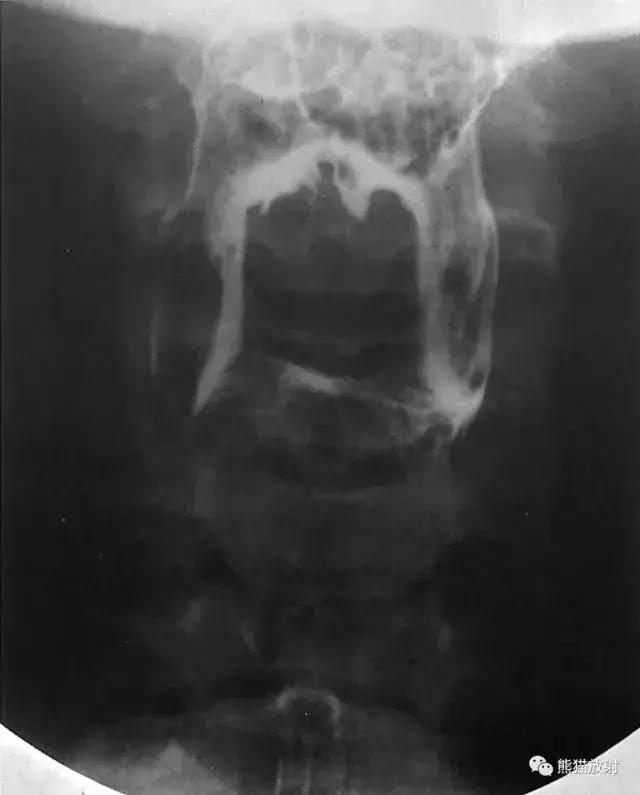

一、下咽部(前后位)

图1 下咽部造影(前后位)

图2 下咽部解剖(前后位)示意图。1 咽腔,2 舌会厌外侧襞,3 会厌谷,4 会厌,5 梨状隐窝,6 食管